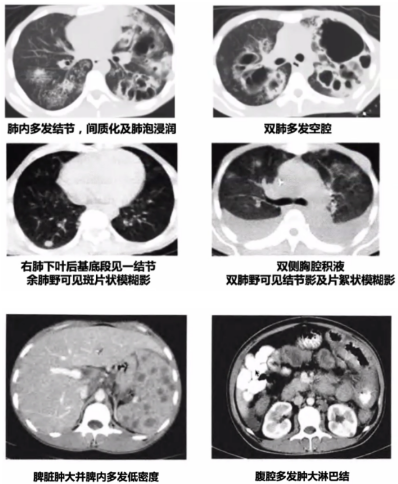

相关文献也提示,TSM的影像学既可以表现为肺内多发结节,也可以有多发空腔样改变,还可以伴有双侧胸腔积液,甚至引起播散性感染,导致腹腔淋巴结肿大,脾大,脾内多发低密度病灶(图17)。有时PET-CT直接回报肺癌、癌性淋巴管炎、纵隔淋巴结转移,或直接回报疑似淋巴瘤。

图片

图17  TSM患者影像学表现

从上述病例的影像学可以看到,TSM的影像学表现多种多样,包括大片实变、结节、磨玻璃改变、粟粒样病变、肺门或纵隔淋巴结肿大、胸腔积液、空洞、坏死,以及细菌性肺脓肿,内壁光滑,甚至有气液平面,这与我们既往所认识的真菌影像学特征有所不同。研究显示,大部分HIV阳性患者胸部影像学表现形式多样,45.6%表现为斑片状浸润影或局限性肺实变,较少形成空洞病灶(8.0%)。HIV阴性TSM患者胸部影像学表现与HIV阳性患者相似,主要表现为肺部浸润影伴或不伴间质性改变,亦常出现胸腔积液。